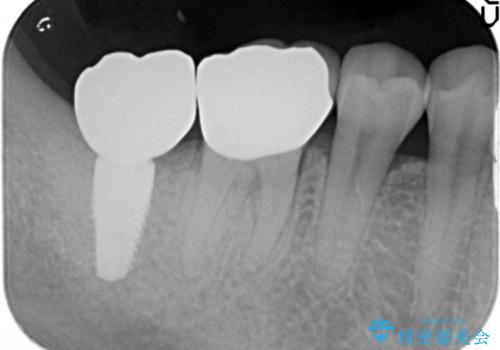

- 費用(概算)

- 50万円(ストローマンインプラント・骨造成・チタンカスタムアバットメント・ジルコニアクラウン)費用は治療当時の料金となります

歯を失い、将来的にインプラントを埋入し咬合機能を回復していく場合、十分な骨量の確保は重要です。

今回抜歯後、骨が十分に確保できないとの判断から抜歯と同時に骨補填剤の填入を行いました。